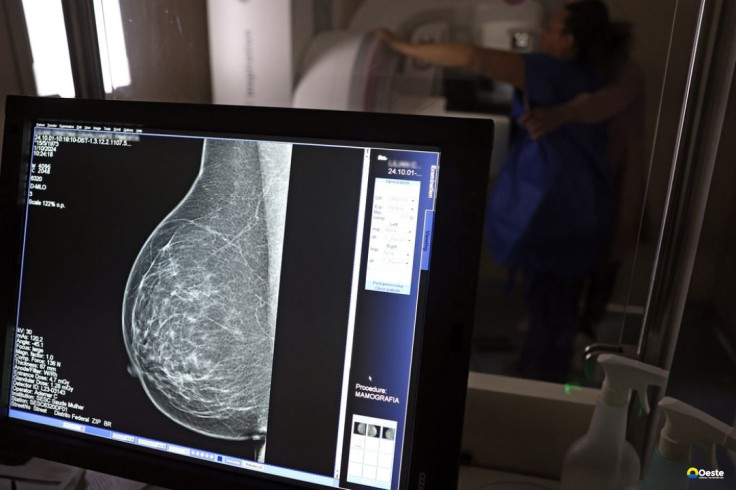

Falta de acesso a mamógrafos limita prevenção do câncer de mama

O país tem 6.826 equipamentos registrados, sendo 96% em funcionamento. Metade deles está disponível no Sistema Único de Saúde (SUS), responsável por atender 75% da população. Isso equivale a 2,13 mamógrafos por 100 mil habitantes dependentes do SUS.

O Brasil tem uma cobertura muito baixa de mamografias: 24%. O ideal recomendado pela Organização Mundial da Saúde é de 70%. Mesmo em lugares como o estado de São Paulo, que tem a maior concentração de mamógrafos do país, a taxa gira em torno de 26%.

Em setembro, o Ministério da Saúde ampliou as diretrizes de rastreamento, recomendando que mulheres entre 40 e 49 anos realizem mamografias, mesmo sem sintomas. De acordo com o Instituto Nacional do Câncer (Imca), mais de 73 mil mulheres recebem o diagnóstico de câncer de mama anualmente no Brasil.

“O que é efetivo na redução da mortalidade é você descobrir o tumor antes de ter sintoma clínico. Quanto menor o tumor, melhor para a gente descobrir o tratamento e maior a chance de cura. E a gente só consegue fazer isso com exames de imagem", diz Ivie.

Ela explica que no caso de diagnóstico de um câncer de mama com menos de 1 cm, a chance de cura é de 95% em cinco anos, independentemente se ele é do tipo mais agressivo. "E esses tumores só vão ser detectados na mamografia. Essas pessoas que têm que ir fazer mamografia são mulheres saudáveis. Não são mulheres doentes”, acrescenta.